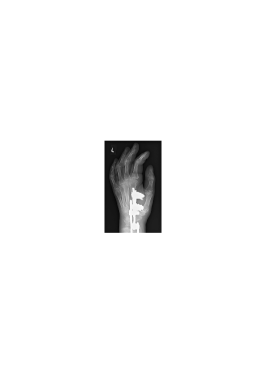

We illustrate now the suitability of the proposed mixed dictionary to produce high quality approximations of the set of X-ray medical images shown in Fig. 3. This set of twenty images is the Lukas 2D 8 bit medical image corpus, available on [33].

Image PSNR DWT DCT OMP2D HBW Hand1 48.1 30.0 26.4 39.0 72.6 Foot1 48.6 26.6 26.1 30.4 44.9 Foot0 48.6 25.5 26.1 42.7 65.2 Head0 47.4 25.3 24.3 51.9 63.2 Knee1 48.0 22.7 23.0 34.5 59.8 Sinus0 47.1 18.9 18.7 31.3 46.7 Hand0 48.8 18.6 18.7 32.2 47.9 Head1 46.4 17.5 15.1 38.3 44.4 Knee0 49.1 17.4 17.5 33.2 45.9 Sinus1 45.8 17.2 17.1 29.5 43.0 Breast0 44.3 15.7 15.3 36.7 41.0 Breast1 44.3 11.5 11.2 27.7 29.7 Thorax0 44.1 10.6 10.9 25.1 27.4 Thorax1 43.4 10.3 9.6 25.4 26.3 Leg0 48.9 8.2 8.4 21.2 22.3 Leg1 49.2 5.8 5.9 15.1 15.4 Pelvis1 44.3 4.8 4.7 12.3 12.6 Pelvis0 44.4 4.6 4.7 12.4 12.6 Spine1 47.0 3.5 3.6 9.3 9.4 Spine0 47.4 2.9 2.8 7.1 7.7